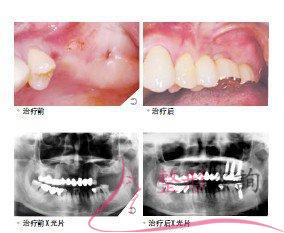

做多顆牙種植治療效果怎么樣?效果保持時(shí)間多久?

一、做多顆牙種植治療方式及過(guò)程

一、治療方式

種植

二、治療過(guò)程

①、拔除沒(méi)有治療價(jià)值的牙齒

②、備制種植窩

③、備制螺紋

④、植入種植體

⑤、縫合創(chuàng)口

⑥、帶上牙冠

二、做多顆牙種植治療效果怎么樣

1.種植后的牙齒,咀嚼壓力可以通過(guò)人工牙根直接傳遞至牙槽組織,因此可以承受更大的咀嚼壓力,咀嚼效率較傳統(tǒng)假牙有大幅度提高。

2.由于種植體深植于患者的牙槽組織,因此種植牙修復(fù)后的牙齒,可以像真牙一樣扎根在患者的口腔里,比傳統(tǒng)假牙更加穩(wěn)固牢靠。

3.種植牙可以獲得與天然牙功能、結(jié)構(gòu)以及美觀(guān)效果十分相似的修復(fù)效果。

三、做多顆牙種植效果保持時(shí)間多久

取決于求美者的術(shù)后日常護(hù)理。

四、做多顆牙種植治療次數(shù)

一次。